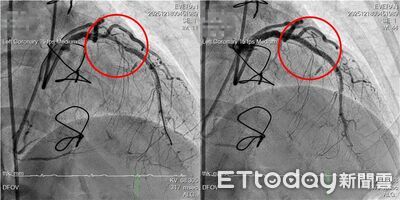

57歲的李小姐多年飽受冠狀動脈疾病所苦,歷經心導管支架治療與冠狀動脈繞道手術,仍反覆出現胸悶與放射性背痛。長安醫院心血管中心主任盧炯睿醫師檢查後發現,患者繞道血管已阻塞,原支架血管亦出現嚴重「支架內再狹窄」,並合併高度鈣化,醫療團最終採用「IVL血管內震波碎石術」,成功打通血流。 《詳全文...》